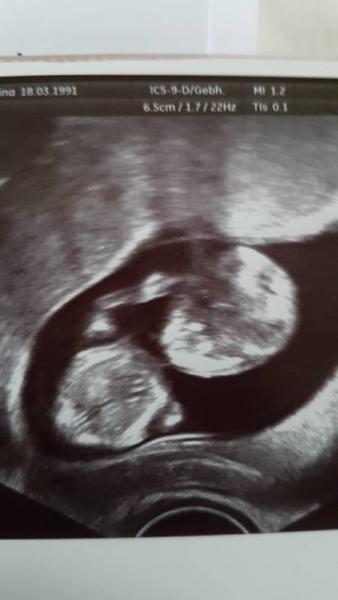

Hallo ihr, es ist lange her und da ich nun wieder Grund habe in diesem Forum unterwegs zu sein dachte ich dass ich mich mal auf die Suche nach euch mache. Vielleicht schaut ja doch der ein oder andere noch einmal hier rein :-). Damals war ich als Kara Kaleeshi hier bei euch und hatte Ende 2015 die fürchterliche Fehlgeburt vor meinem Sofa, vielleicht erinnert sich ja der ein oder andere noch ein bisschen daran. Ich hoffe es geht euch und euren Familien allen gut < 3 Wir sind damals an der Geschichte zerbrochen und im bösen auseinander gegangen, wir haben auch leider nie heraus gefunden was damals wirklich ursächlich für die FG war. Ich war es irgendwann auch einfach Leid muss ich ehrlich sagen und war froh dass ich abschließen konnte. Heute bin ich mit meinem besten Freund seit Kindertagen zusammen und wir wollen auch heiraten :-) ich bin aktuell in der 13. SSW und bis auf eine fiese Hyperemesis gravidarum absolut komplikationslos :-) Ich häng euch mal ein Bild an, man merkt dieses Kind wird so rebellisch wie seine Eltern :'D Ich wünsche euch eine wunderschöne Zeit und ein erfülltes Leben :-) GLG Kara

Bild zu Hallo ihr Lieben :-) - Forum für Juni - Mamis